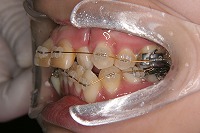

26歳1か月

前歯が出ていて歯並びが悪い事を主訴に来院された、26歳1か月の女性です。診断「歯と歯槽基底の大きさの不調和による叢生」上顎は右側第1小臼歯と左側の犬歯、下顎は抜歯をせず治療を行いました。